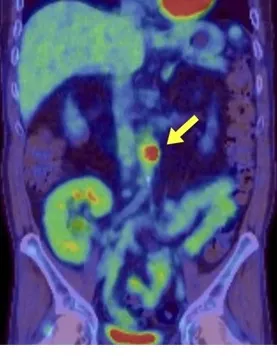

2. PET/CT (16º dia): Captação de FDG no mesmo local, confirmando inflamação ativa – diagnóstico: aortite infecciosa por Salmonella.

Achados de imagem na aortite infecciosa. (A) TC no 6º dia mostra abaulamento focal e calcificação da parede anterior da aorta abdominal, próxima à artéria mesentérica superior, com borramento da gordura ao redor (sinal de inflamação). (B) A PET/TC no 16º dia evidencia captação de fluorodeoxiglicose (FDG) na mesma região, indicando inflamação ativa.

5. PET/CT é ferramenta diagnóstica-chave para confirmação e acompanhamento de inflamação vascular em casos duvidosos.